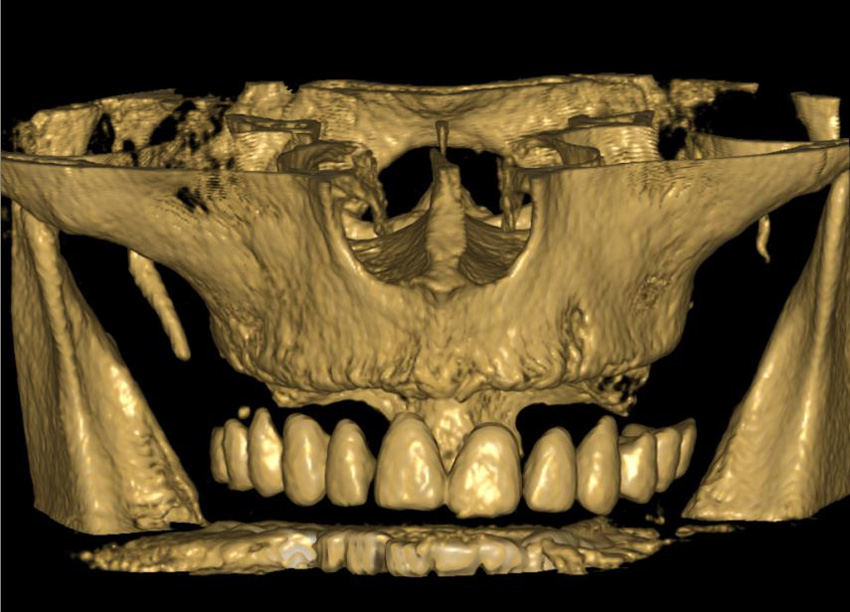

Lékař si vytvoří všechny typy zobrazení potřebných pro naplánování – tedy 2D snímky (panoramatický), příčné řezy i 3D model.

Vidí zde i důležité anatomické útvary – čelistní dutinu, průběh nervu atd. Po proměření množství kosti – šířky i výšky vybere z databáze vhodný typ implantátu a umístí ho do požadované lokality. Ihned vidí jeho pozici ve všech 3 rovinách a na všech snímcích i 3D modelu. Může upravovat podle potřeby jeho pozici, sklon atd.

Všechny vybrané a správně umístěné simulované implantáty se ukládají do „počítačové karty“ pacienta s jejich pozicí, délkou, průměrem, typem i sklonem. V programu také lékař navrhuje chirurgické šablony pro řízenou nebo navigovanou implantaci. Lékař i pacient tedy ještě před vlastní operací vidí, jak by mělo ošetření probíhat a vypadat.